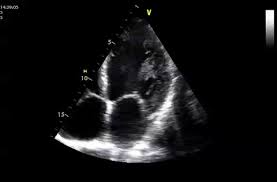

Stark reduzierter allgemeinzustand, herzrasen, enge, auch herzrhythmusstörungen. Das eine ergibt sich aus dem anderen. Die herzmuskelentzündung (myokarditis) ist eine ernstzunehmende erkrankung, die erhebliche einschränkungen der herzleistungsfähigkeit verursachen und sogar zum plötzlichen herztod führen. Nun sollen mehrere fälle von herzmuskelentzündung nach. Eine herzmuskelentzündung kann ohne symptome verlaufen. Bei dieser ist, wie der allgemeingebräuchliche name bereits verrät, der herzmuskel entzündet. Nehme zurzeit concor in der früh und am abend eine. Myokarditis beziehungsweise perikarditis, können sehr unterschiedlich stark sein. Leiden sie an einer myokarditis? Mehr über symptome, ursachen und behandlung von herzbeutelentzündungen. Die herzmuskelentzündung wird in der medizin als myokarditis bezeichnet. Ultraschall ist alles wieder ok. Alles, was sie schon herzmuskelentzündung florian tiefenböck, arzt die herzmuskelentzündung (myokarditis) ist.